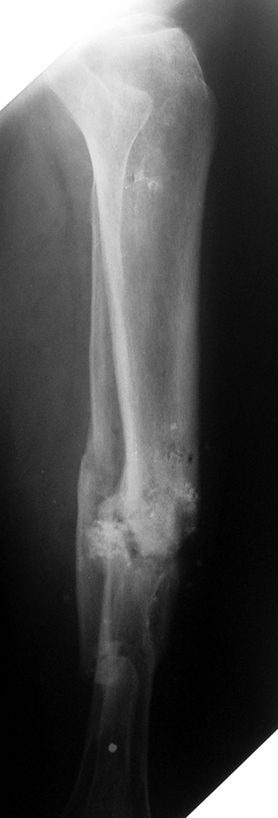

Tibia Osteomyelitis

Chronic Osteomyelitis

Chronic osteomyelitis leads to necrosis of bone and soft tissues. Dead bone is a nidus which hosts pathogenous microorganisms. Defence mechanisms of the host is usually not in optimum condition to deal with microorganisms. Antibiotics can’t reach the infection site because blood flow is disrupted. For these reasons, dead bone has to be completely removed by radical debridement.

Appropriate radical debridement necessitates excision of all necrotic bone and soft tissues, and frequently causes instability at the involved extremity. The remaining bone and soft tissue defect has to be fixed and reconstructed. The distraction osteogenesis method of Ilizarov is used successfully for achievement of union, correction of the deformity, elimination of limb length inequality and reconstruction of segmental bone defects.